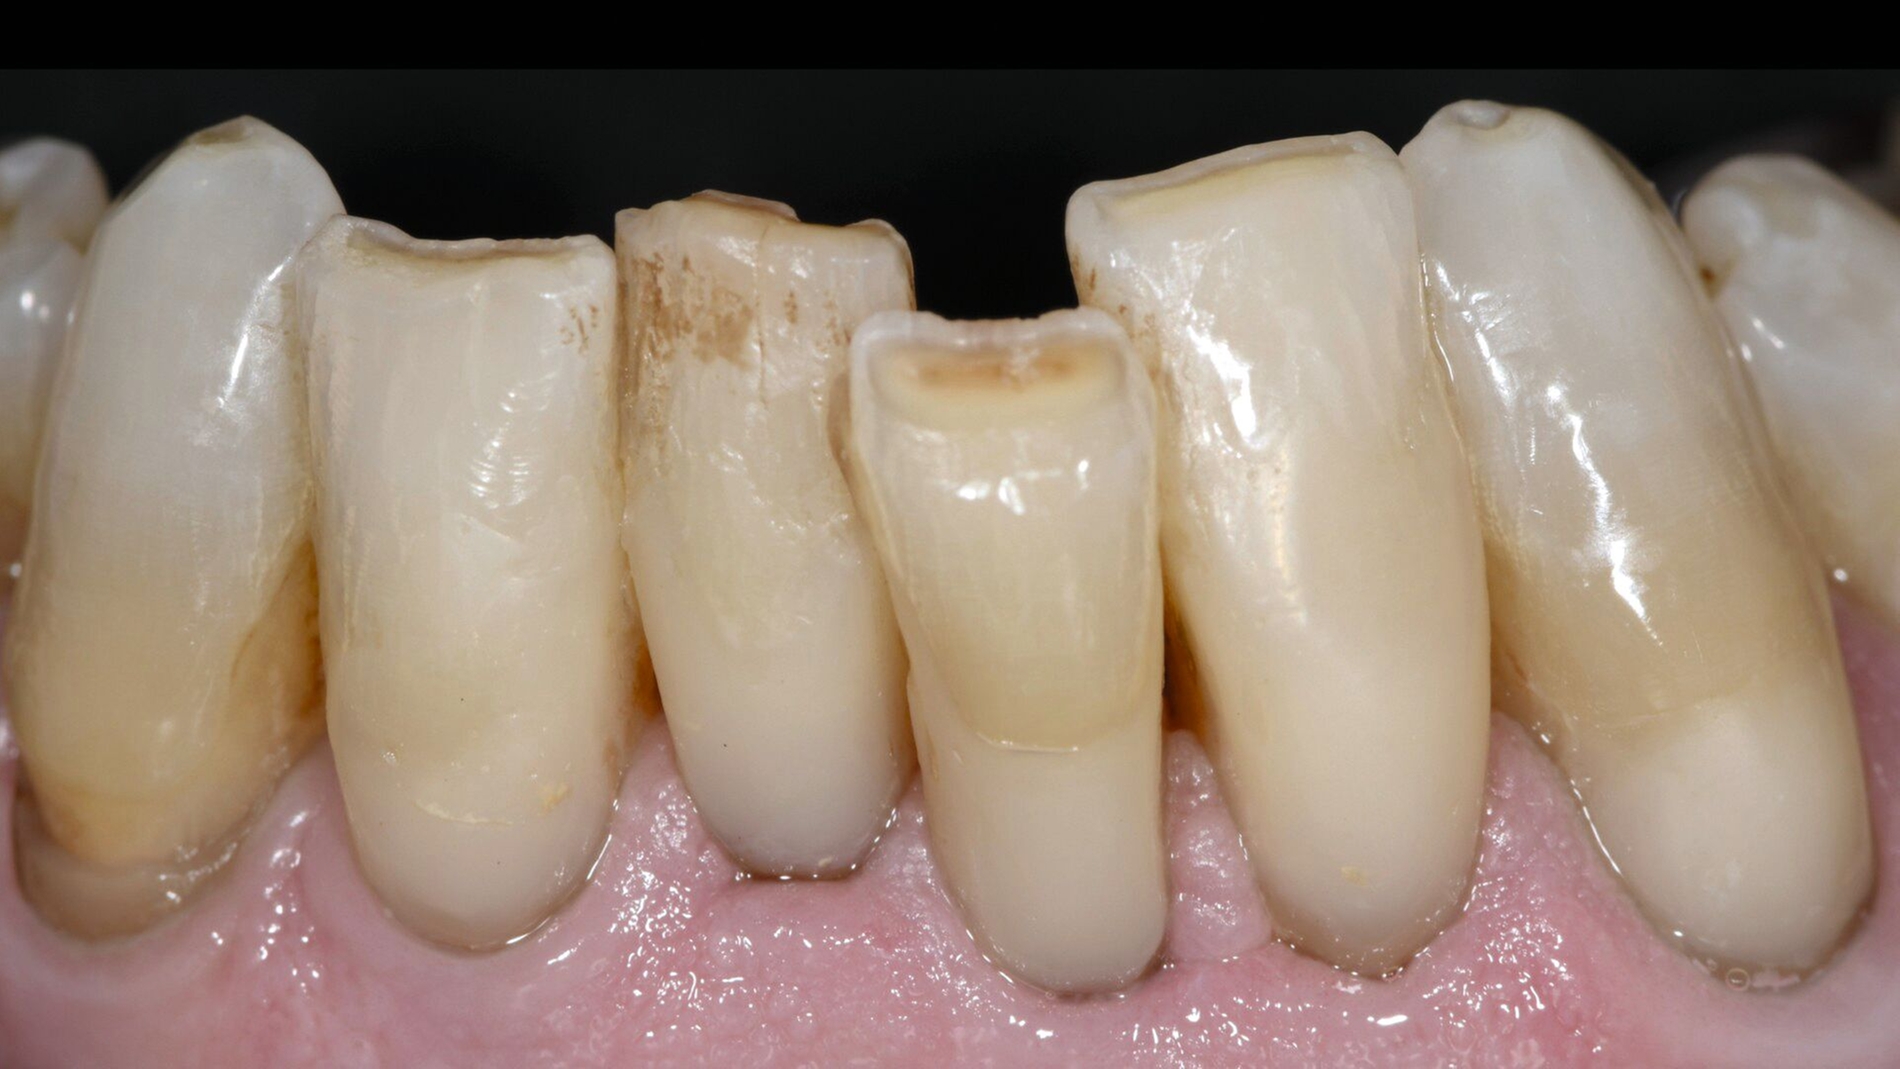

Ein sich seit vielen Jahren bei mir in Behandlung befindlicher 75-jähriger Patient klagte zunehmend über Hypersensibilitäten an den unteren Frontzähnen, die im Zahnhalsbereich ausgeprägte Zahnhartsubstanzdefekte aufwiesen (Abbildungen 1a–1d). Die Mundhygiene wurde als gut eingestuft. Möglicherweise waren die vorliegenden Zahnhalsdefekte als sogenannte Putzdefekte zu klassifizieren, wie sie bei intensiven Mundhygienebemühungen häufig zu beobachten sind.

Mit zunehmendem Alter hatte der Patient allerdings Mühe, die schwer zugänglichen Defekte adäquat zu reinigen. Zudem musste man befürchten, dass es bei weiterem Abbau der Zahnhartsubstanz in diesen Bereichen zu einem Verlust der Zahnintegrität oder einer Pulpaexposition kommt. Daher wurde entschieden, die besonders stark betroffenen Zähne 31, 32, 41 und 42 mit Kompositrestaurationen im Zahnhalsbereich zu versorgen.

Zwei Jahre nach Restauration der unteren Inzisivi wurde deutlich, dass der Patient auch an Zahn 33 den vorliegenden Zahnhalsdefekt nicht mehr ausreichend reinigen konnte. Daher wurde entschieden, auch diesen Zahn mit einer Kompositrestauration zu versorgen (Abbildung 1d).